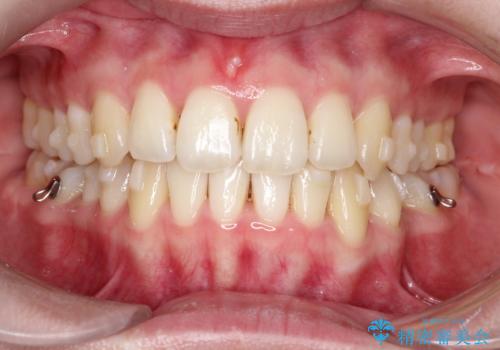

【インビザライン】 前歯の反対咬合を治したい

- なるべく目立たない装置を希望されたためインビザラインにて治療を行いました。

左下5番は先天性欠損のため乳歯は抜歯しインプラントにて欠損補綴しています。